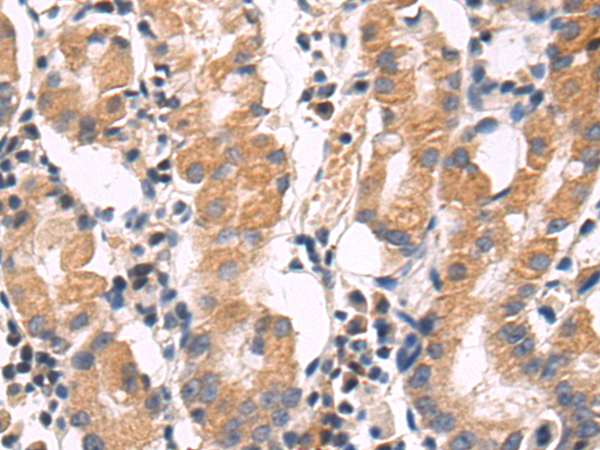

分类: 科研抗体货号: P01946别名: EGP1; GP50; M1S1; EGP-1; TROP2; GA7331; GA733-1应用: IHC反应种属: Human, Mouse, Rat